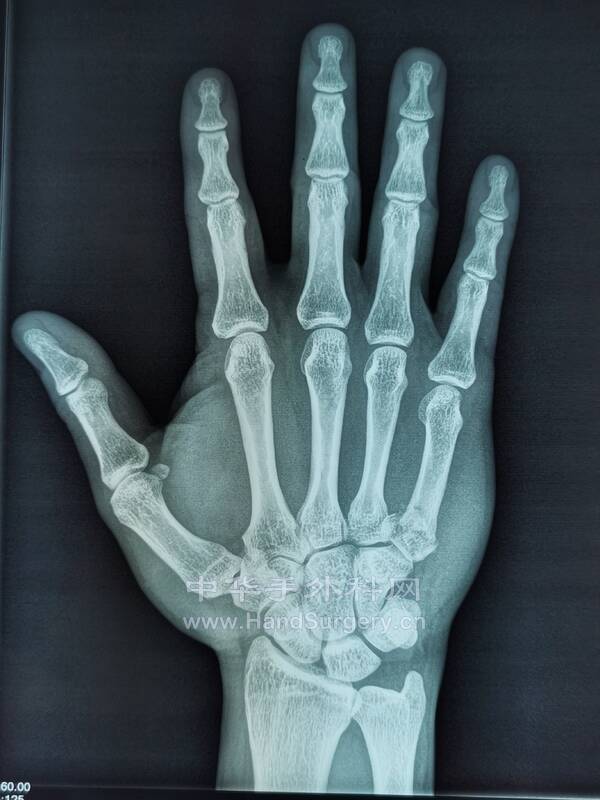

33闭合复位克氏针横向固定治疗第5掌骨基底骨折.pdf

1.48 MB, 下载次数: 79

微信图片_20220614224346.png

微信图片_20220614224350.png